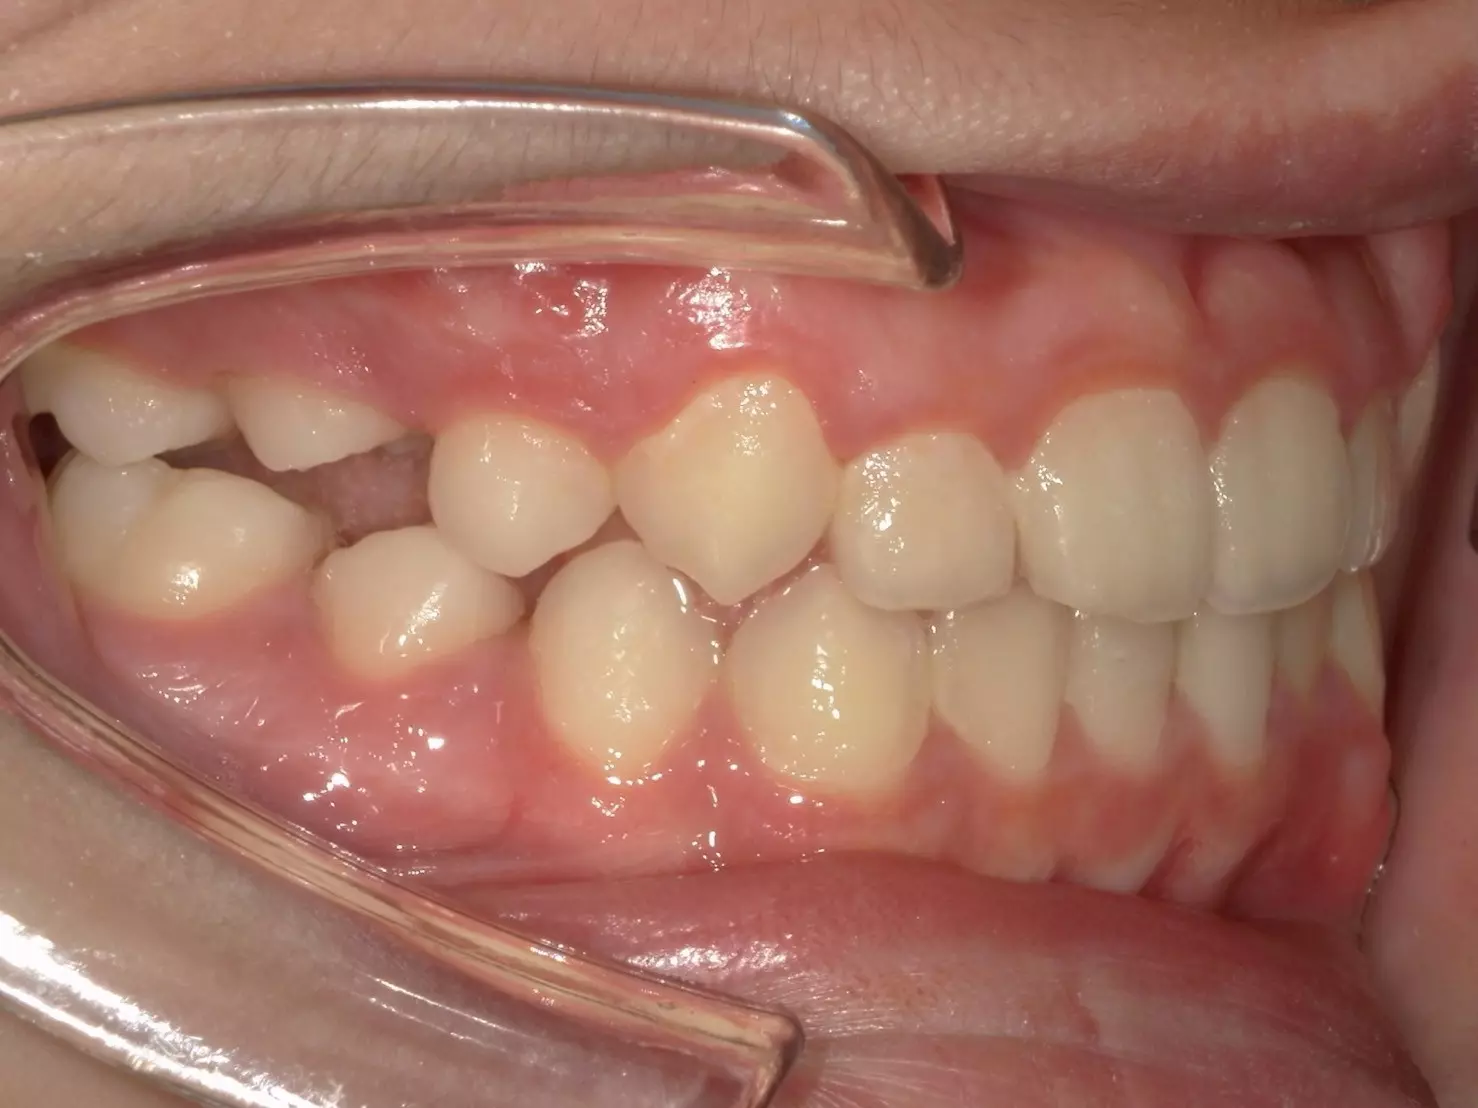

↑治療前

這位 11 歲的男孩,因為前牙錯咬問題導致上顎的牙弓變窄,前牙空間不足,不僅影響到進食,連笑容都變得不自然。他的父母觀察到,孩子不太喜歡吃東西,也漸漸在笑的時候變得保守,甚至開始避免拍照。

經過仔細檢查後,我們確認他屬於功能型第三類咬合異常 (Functional Class III)。這和大家熟知的「骨性戽斗」不同,他的狀況主要是因為牙齒排列影響了上顎的發育。這類型的咬合異常,如果沒有及早治療,可能會影響上顎的生長空間,進而讓整體顏面外觀及咬合狀態惡化。